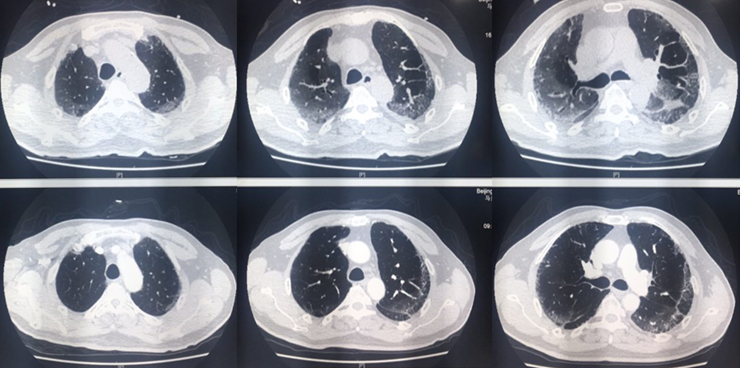

对于急性重型ILD,一定要做到早期识别、早期诊断和早期治疗。我们团队救治成功的病例基本上是在1周之内开始大剂量糖皮质激素治疗。这是我们近期收治的病例,有上呼吸道感染的前驱症状,胸部CT可见明显实变,磨玻璃影,小叶间隔增厚,患者快速进展至呼吸衰竭。

气管插管后完善病原学筛查,尽快给予皮质激素冲击治疗,1周后,患者胸部CT可见病变明显缓解,患者于第10天拔管,后续情况非常稳定。对此类患者,只有平安度过急性期,才有机会进行后续治疗,患者也才能获得良好的预后。

图片